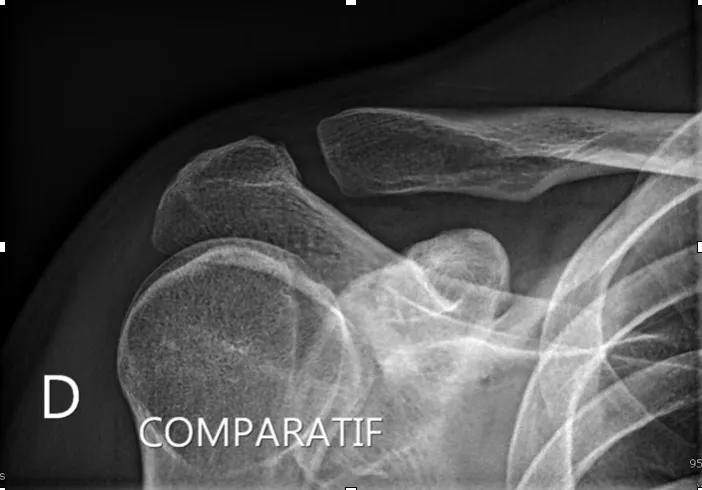

Dans un premier temps des radiographies permettent d'avoir une orientation diagnostique en corrélation avec l'examen clinique du chirurgien. Des clichés comparatifs (des deux épaules) permettent d'affiner le diagnostic. Un scanner avec des reconstructions tridimensionnelles peut être utile dans certains cas.